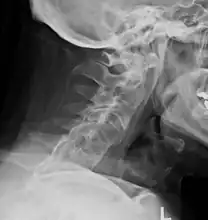

X-rays

The earliest changes demonstrable by plain x–ray shows erosions and sclerosis in sacroiliac joints. Progression of the erosions leads to widening of the joint space and bony sclerosis. X-ray spine can reveal squaring of vertebrae with bony spur formation called syndesmophyte. This causes the bamboo spine appearance. A drawback of X-ray diagnosis is the signs and symptoms of AS have usually been established as long as 7–10 years prior to X-ray-evident changes occurring on a plain film X-ray, which means a delay of as long as 10 years before adequate therapies can be introduced.[19]

Options for earlier diagnosis are tomography and MRI of the sacroiliac joints, but the reliability of these tests is still unclear.